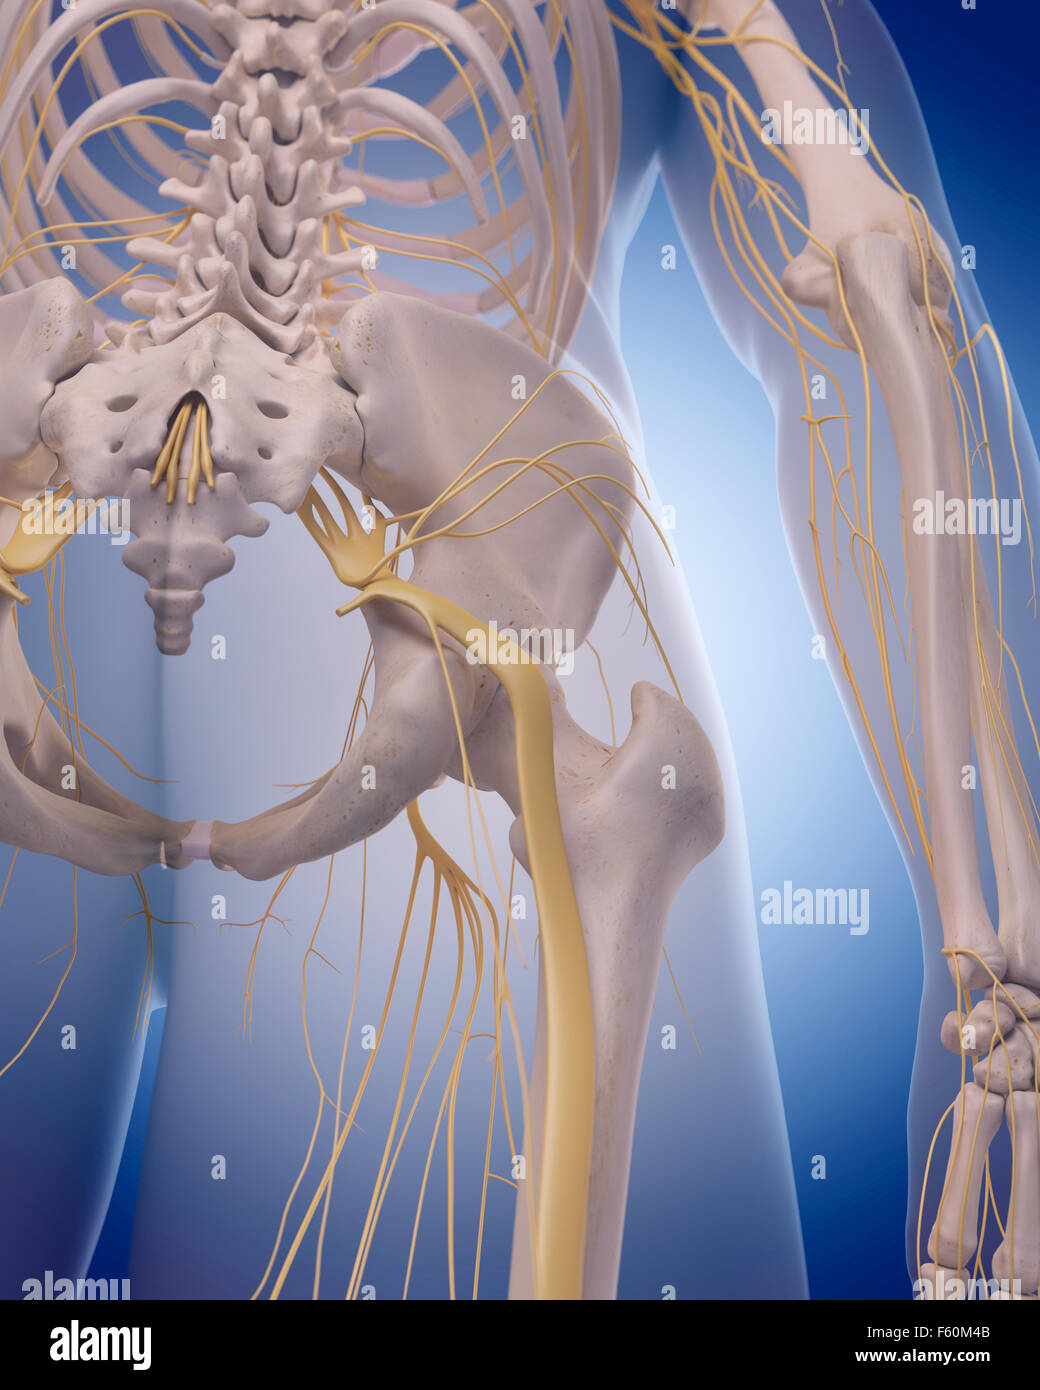

Illustration - médicalement exacts du nerf sciatique Banque D'Imageshttps://www.alamyimages.fr/image-license-details/?v=1https://www.alamyimages.fr/photo-image-illustration-medicalement-exacts-du-nerf-sciatique-89755579.html

Illustration - médicalement exacts du nerf sciatique Banque D'Imageshttps://www.alamyimages.fr/image-license-details/?v=1https://www.alamyimages.fr/photo-image-illustration-medicalement-exacts-du-nerf-sciatique-89755579.htmlRFF60M4B–Illustration - médicalement exacts du nerf sciatique